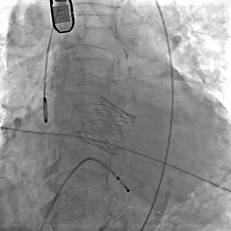

缓慢脱钩

瓣膜无位移

脱钩后造影

瓣膜位置可,无瓣周漏

左冠切线造影,瓣膜同轴性佳,位置可,无瓣周漏